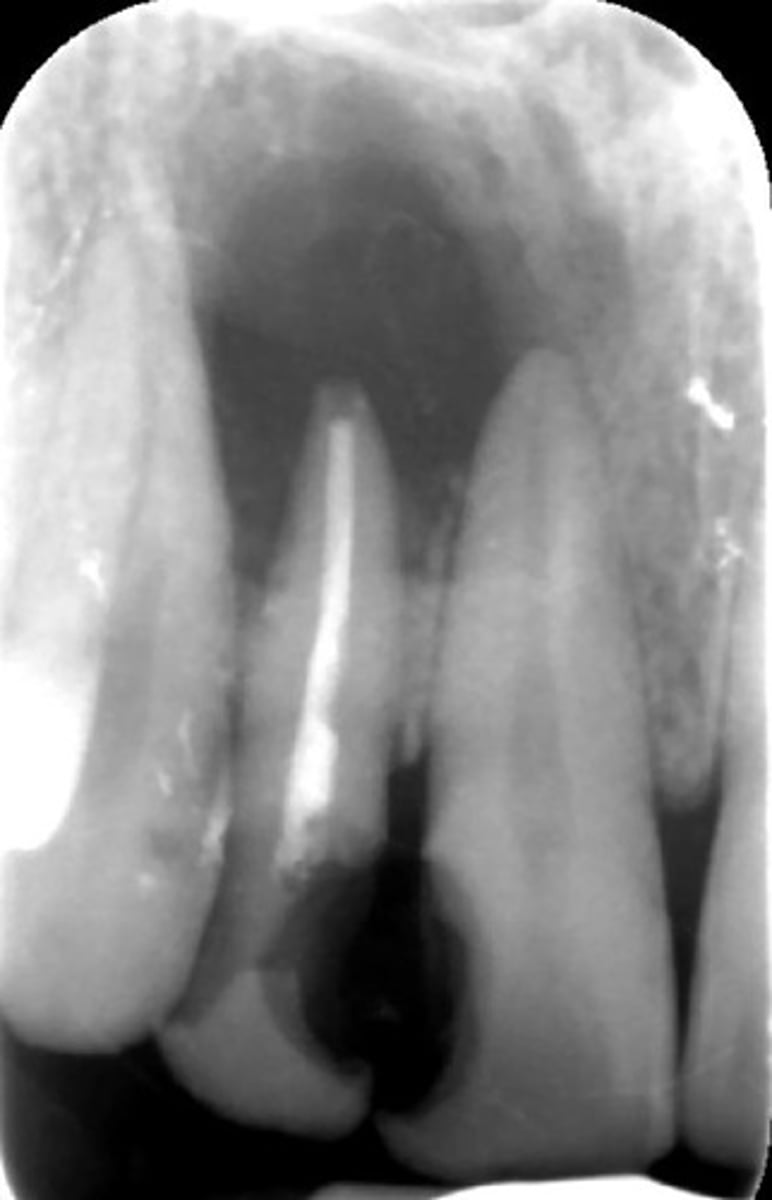

how would you describe this lesion?

A. well-defined, periapical radiolucent lesion associated with #24 and 25

B. ill-defined, periapical radiolucent lesion associated with #24 and 25

C. well- defined, multilocular periapical lesion associated with tooth number 24 and 25

D. mixed density, periapical lesion associated with teeth number 24 and 25

- Also note loss of apical lamina dura of 24, 25

What category would this lesion be part of?

Dysplasia

What would be a differential diagnosis for this lesion?

PCOD (stage 1)